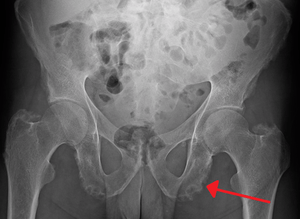

| Enthesopathy of the pelvis likely due to ankylosing spondylitis | |

Enthesopathy of the pelvis likely due to ankylosing spondylitis